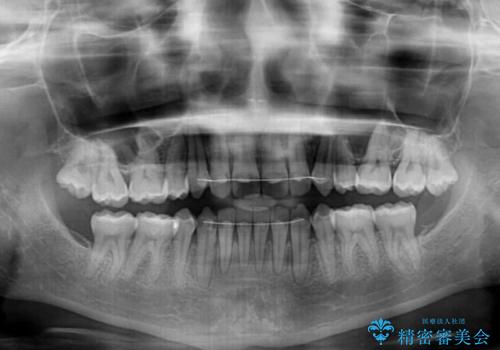

- 以前の矯正治療の後戻りにより、上の前歯にスペースができたことを気にして来院された患者様です。

インビザラインを用いて前歯のスペースを閉じつつ、上下の咬み合わせを構築していくこととしました。